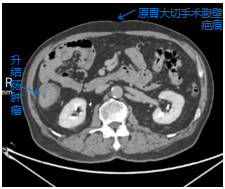

今年65岁的王先生来自邻近省份,被确诊为升结肠癌,同时合并有冠心病、糖尿病史,既往有腰椎内固定术、因房颤行心脏射频消融术病史,更棘手的是,他在多年前因胃溃疡穿孔、阑尾炎接受过传统的开腹胃部分切除术、阑尾切除术。此次患病,当地医院评估认为,其腹腔内因既往两次的胃肠道手术可能存在广泛粘连,解剖结构改变,再次行腹腔镜手术难度极大,易导致副损伤,建议行开放手术。然而,开放手术创伤大、恢复慢,王先生及其家属渴望能寻求一种更微创、更快速的康复方案。经多方打听和朋友推荐,他们了解到我院胃肠外科二病区在处理复杂腹腔肿瘤及腹腔镜微创手术方面经验丰富,毅然决定跨越省界,前来就医。

面对患者的这份沉甸甸的信任,我院胃肠外科二病区高度重视。科主任组织结直肠癌MDT团队及全科医护人员进行了深入的术前讨论。专家们一致认为,患者合并有较多内科疾病病史,围手术期治疗各科紧密协作,可确保基础疾病平稳控制;既往的开腹手术史,必然导致腹腔内脏器与腹壁、肠管之间形成的粘连,这如同在腹腔内设置了一个“迷宫”,使得再次手术的视野暴露、组织分离变得异常困难,术中损伤肠道、血管等重要组织的风险显著增加。